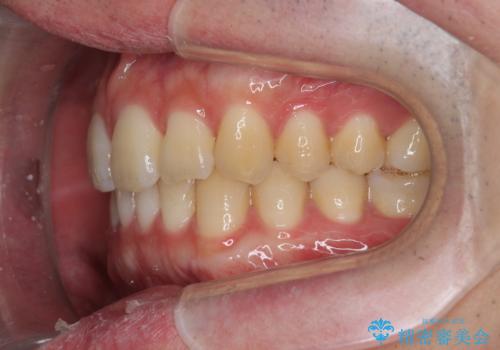

前歯のがたつきをなおしたい マウスピース矯正

- 気になる前歯のがたつきをきれいにしたい。と矯正治療を希望され来院されました。

大きな歯列の乱れはないため、倒れ込んでいる奥歯の傾きの改善、前歯のがたつきを改善する治療を計画します。

見た目が良くなっただけではなく、歯ブラシがしやすくなった!と治療後の歯並びに喜んでいただくことができました。